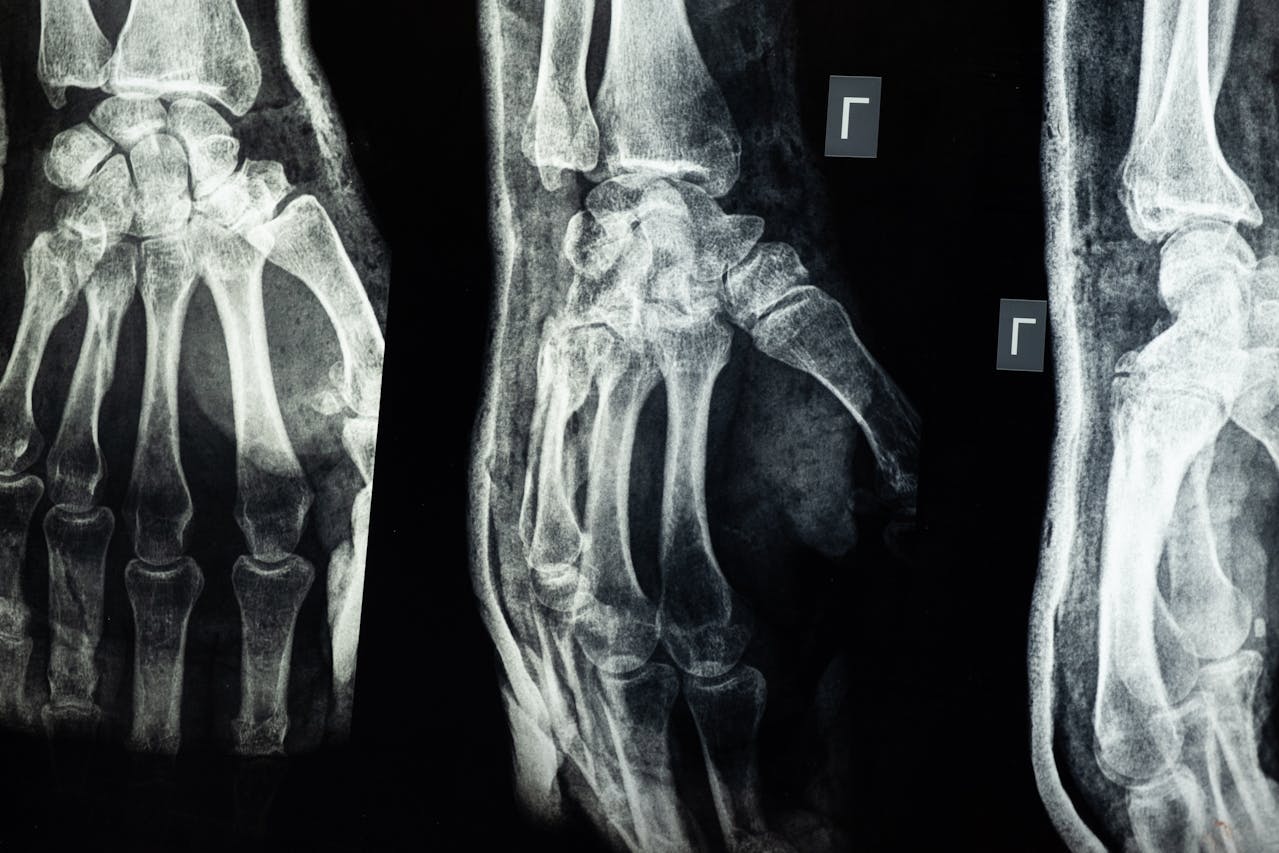

Osteoporosis is a condition where your bones lose strength, making you more likely to fracture (break) a bone – even after just a minor bump or fall.

Having osteoporosis doesn’t mean you will definitely break a bone. But it does mean you’re at higher risk than the average person. There are ways of lowering your risk of broken bones – also known as ‘fragility fractures’ – and to live well with osteoporosis.

An easily broken bone is often the first sign that your bones have lost strength.

One of the most-common broken bones caused by osteoporosis is the wrist – often the result of putting an arm out to break a stumble or fall.

Strong bones should be able to withstand a bump, or the impact of a fall from standing height. So if you’ve broken a bone easily, speak to your doctor. This is especially important if you have other risk factors for osteoporosis.